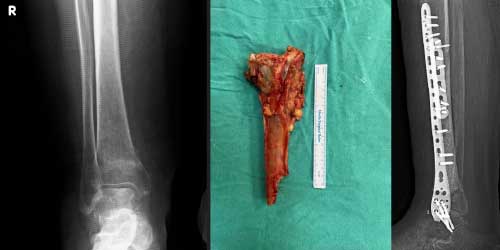

Tedavide başarıyı artıran en önemli etkenlerden biri ameliyat öncesi iyi bir hazırlık ve cerrahi planlama yapmaktır. Her şeyden önce tanı doğru konmalı. Bunun için hasta iyi dinlenip, detaylı muayene edildikten sonra tetkikleri dikkatli incelenmelidir.

Her ameliyatın olduğu gibi kemik ve yumuşak doku tümör ameliyatlarının da riskleri vardır. Bu riskleri genel ve yapılan ameliyata özgü olmak üzere kabaca iki başlık halinde gruplandırabiliriz. Öncelikle anestezi ile ilgili risklerin anestezi uzmanı tarafından (...)

Ameliyat sonrası takip ve kontrol hastanın ameliyat masasında uyanması ile başlar. Özellikle damar ve veya siniri ilgilendiren ameliyatlarda hasta ameliyat masasından alınmadan ekstremitenin dolaşımı ve ilgili sinirin fonksiyonu kontrol edilir.